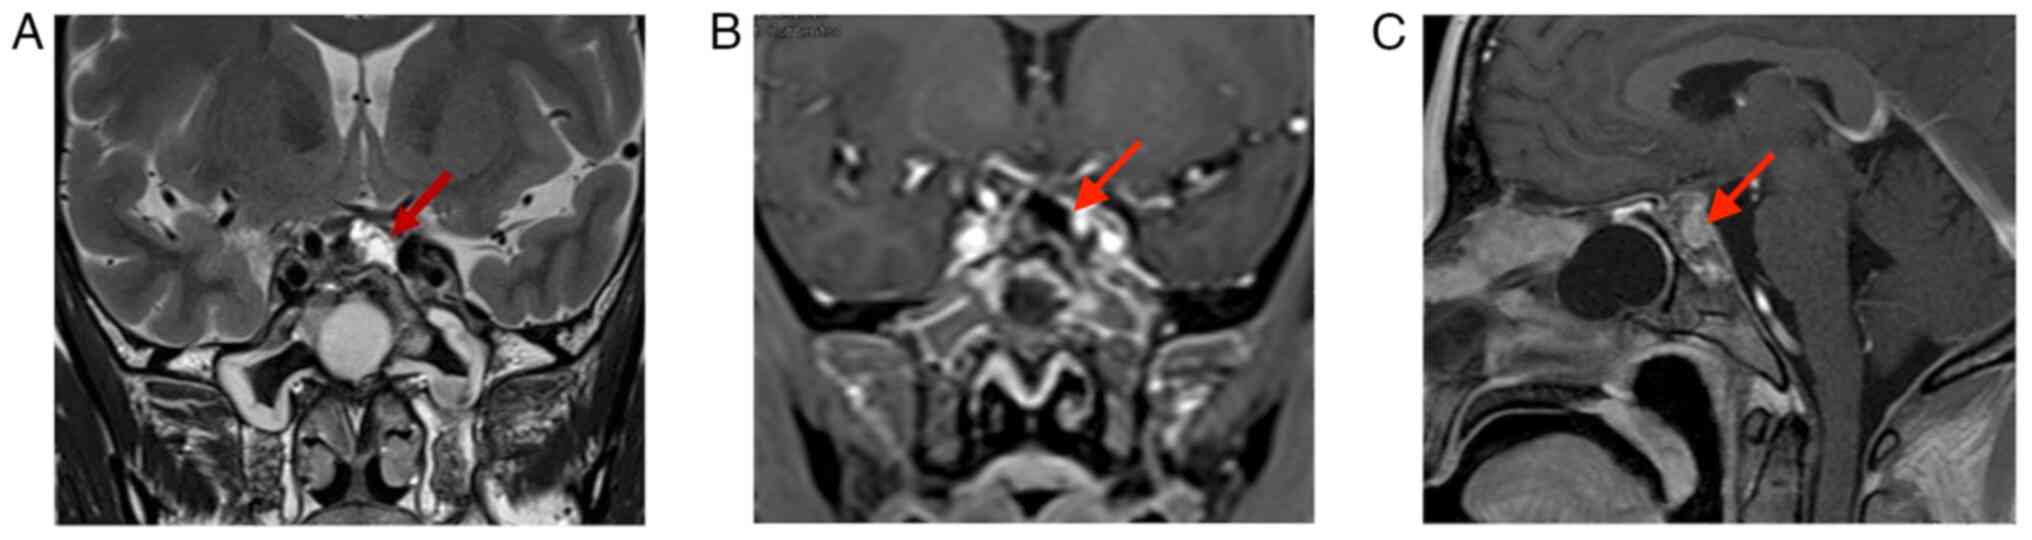

The patient recovered well following surgery without complications. Visual acuity and the visual field condition improved compared with those noted previously. Following surgery, it was explained to the patient that the tumor was recurrent and had a risk of metastasis and routine postoperative radiotherapy was recommended; however, the family refused immediate radiation therapy. At 3 months following surgery, the patient experienced photophobia in the left eye and MRI suggested tumor recurrence in the left cavernous sinus, in the absence of tumor growth in the pituitary fossa (Fig. 6). Therefore, the patient was treated with proton therapy at Shanghai Proton Heavy Ion Hospital (Shanghai, China). The recurrent residual foci were treated with 66 Gray equivalent (GyE)/30 fractions (Fx) and the tumor bed, surgical bed and high-risk area were treated with 54 GyE/30Fx. The process was satisfactory and no radiation therapy-related toxic side effects were observed. At 3 months following the proton therapy, the tumor had slightly receded without any growth (Fig. 7). The patient is being continuously followed up with three-month intervals.

Figure 6.

MRI at 4 months after the second surgery. (A) T1-MRI and (B) enhanced T1-MRI suggest recurrence of the tumor in the left cavernous sinus (red arrows indicate lesion areas). T1-MRI, T1-weighted MRI.

Figure 7.

MRI at three months after proton therapy. (A) T1-MRI; (B) enhanced T1-MRI suggesting the tumor shrank slightly without growth (red arrows indicate lesion areas). T1-MRI, T1-weighted MRI.